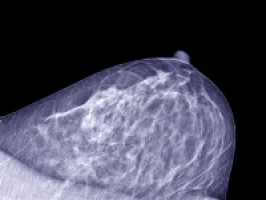

Las mamografías son el método más común para detectar el cáncer de mama, ya que se realizan más de 39 millones de procedimientos al año en Estados Unidos.

Diseñaron y entrenaron un nuevo modelo denominado Mirai, que integra los datos de las mamografías para producir evaluaciones coherentes del riesgo de cáncer de mama en múltiples puntos temporales, como dentro de 1 o 5 años.

Cuando se probó de forma independiente con los datos de 106.615 pacientes de tres hospitales, situados en EE.UU., Suecia y Taiwán, Mirai identificó el 41,5% de las pacientes que desarrollarían cáncer en un plazo de 5 años.

En cambio, los enfoques actuales, como los modelos Tyrer-Cuzick e Hybrid Deep Learning, solo identificaron al 22,9% y al 36,1% de los pacientes, respectivamente. Mirai también fue eficaz en varias razas y etnias, lo que respalda su potencial para informar las directrices de cribado para poblaciones grandes y diversas.